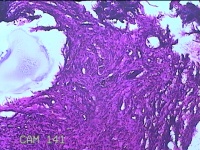

左前臂皮下结节

性别

女

年龄

42岁

临床诊断

皮下结节

一般病史

发现左前臂皮下结节2个月余。

标本名称

大体所见

灰白粉红色带皮肤结节1x0.4x0.3cm一个,表面糜烂,切开结节呈实性,切面灰白粉红色,质软。

图2